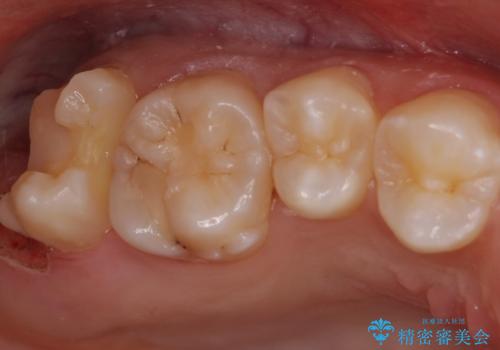

親知らずが原因で手前の歯が虫歯になってしまうことがあります。

今回は親知らずの抜歯後に虫歯治療をしていきました。

親知らずが原因で手前の歯が虫歯になると、その大きさが深かった場合最悪保存が難しくなることもあります。

歯磨きで掃除しきれないような親知らずがある場合は早めに抜くこともおすすめです。